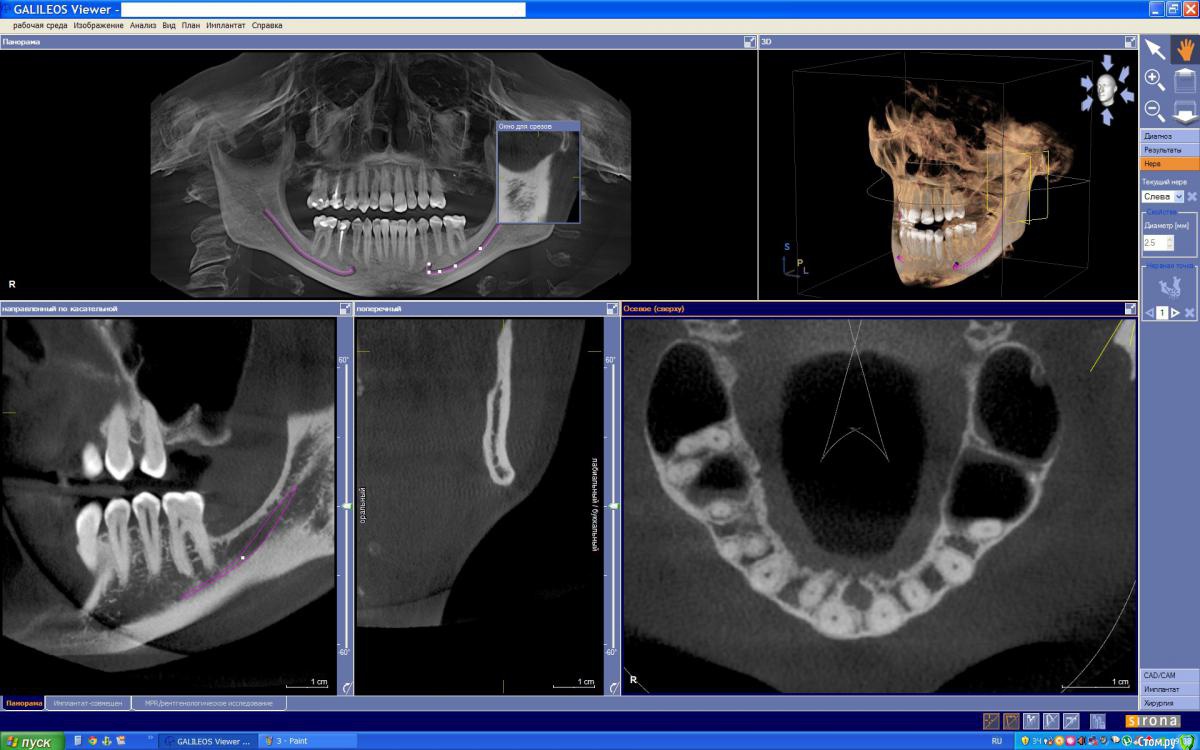

Azara Опубликовано 7 июня, 2015 Поделиться Опубликовано 7 июня, 2015 Здравствуйте, уважаемые специалисты. На консультации хирург-имплантолог изучив снимки КТ сказал, что случай сложный и из-за строения практически отсутствующей кости верхней челюсти нужно заполнять 2 полости, для чего потребуется сделать 2 окна в кости через которые будут проводится 2 операции по заполнению, и возможно что через год потребуется повторное заполнение. Ввиду физиологического строения, нехватку данного зуба я довольно остро ощущаю. Но к сожалению я морально не готова перенести такое добровольное "издевательство" над своим организмом. Врач сказал что на раздумья у меня полгода. Есть ли какая то другая возможность по восстановлению данного зуба без имплантации? Если все же только имплантация то другой способ синус-лифтинга? Зуб удален год назад. Заранее спасибо за ваше мнение. Ссылка на папку со снимками КТ https://yadi.sk/d/OksbhWPth8JVw И скриншоты с КТ Ссылка на комментарий